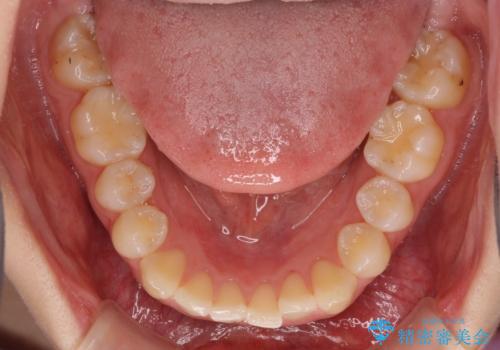

- 前歯のデコボコと上下のクロスバイトを気にして来院された患者様です。

インビザラインを用い、IPR(歯と歯の間を削る)と歯列全体を拡大させることで、歯並びを整えていくこととしました。